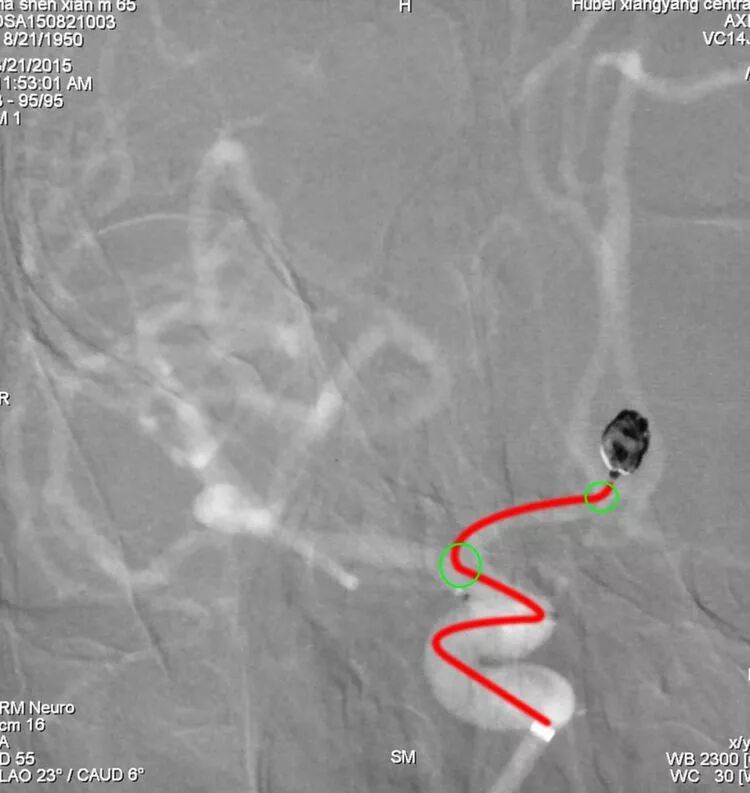

前交通动脉瘤,朝向上方生长,微导管头端塑反向两个弯儿(绿圆圈)呈S形